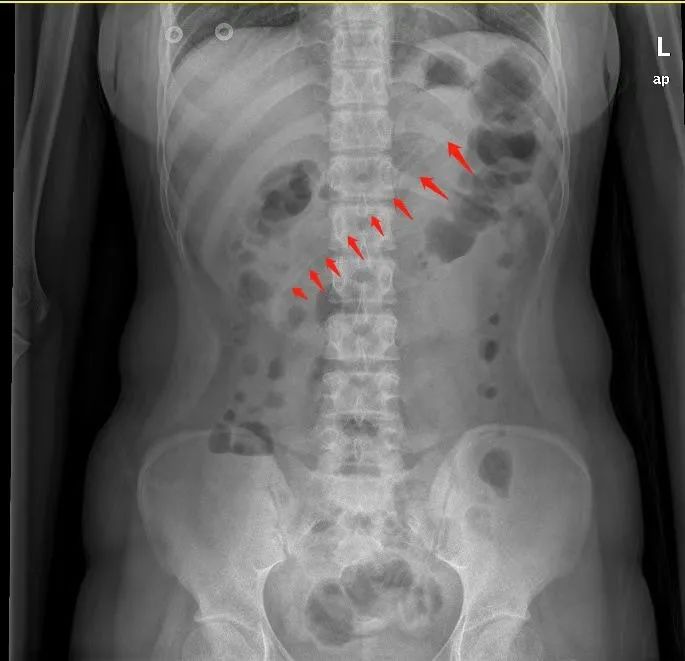

腹部X线检查显示,小李胃中的勺子长达17厘米,因此胃镜下取异物有较大的难度。但如果不取出,患者可能会出现消化道梗阻、出血和穿孔等并发症。因此,胃镜下取出异物势在必行。